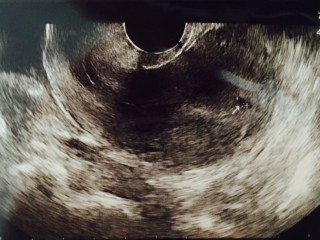

普段生理が遅れることはあまりなく、今回だけ生理が4日遅れて、とりあえず、市販の検査薬を購入してみたらなんと陽性?!翌日産婦人科に行きエコーを、いただきました!次は3週間後にちゃんと心拍を確認できるとのことで、3週間が待ち遠しいです(*^^*)どうか、大きく育ってくれますように